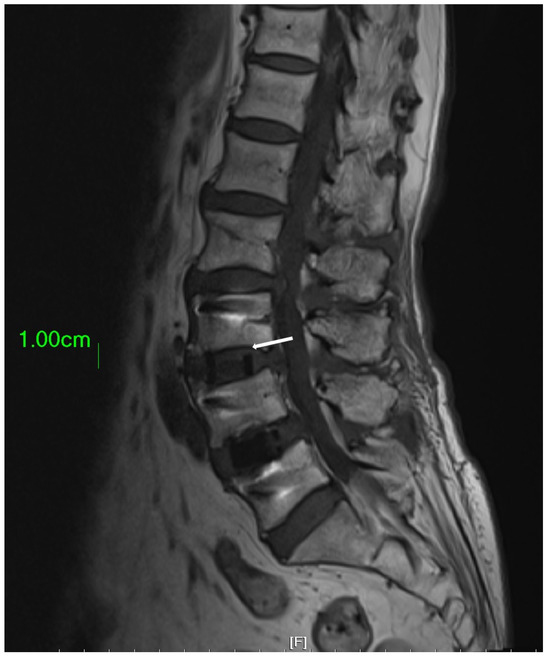

2.1. Model of Spine

2.2. Model of Cage

2.3. Model of Disc